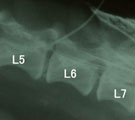

初診時。両後肢の対麻痺で起立不能。 脊髄造影。L4-L6にかけ背腹両方に造影剤の充填欠損がみられ脊髄全体の腫脹が示唆された。 術後2日で自ら起立して食事を食べれるようになった。

経過:受診時、後肢不全麻痺にて起立不能だった。痛覚認知はあった。同日、脊髄造影にてL4-L6に脊髄自体が腫大して生じたような造影剤充填欠損像が認められた。翌日、L4-L6において片側椎弓切除術による脊髄の減圧術を行った。術中、硬膜に接して砂状塊状物あり、後に病理検査で「砂粒腫型髄膜腫」と診断された。術後2日で自分で立って食事を食べれるようになった。7日後には10m位歩けるようになり経過良好であった。